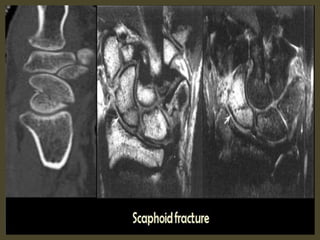

CT images with small cyst formation within the fracture line.

MR Protocol with pre and post-contrast images for fracture.

Scaphoid waist fracture with subtle collapse of the proximal pole, related AVN .